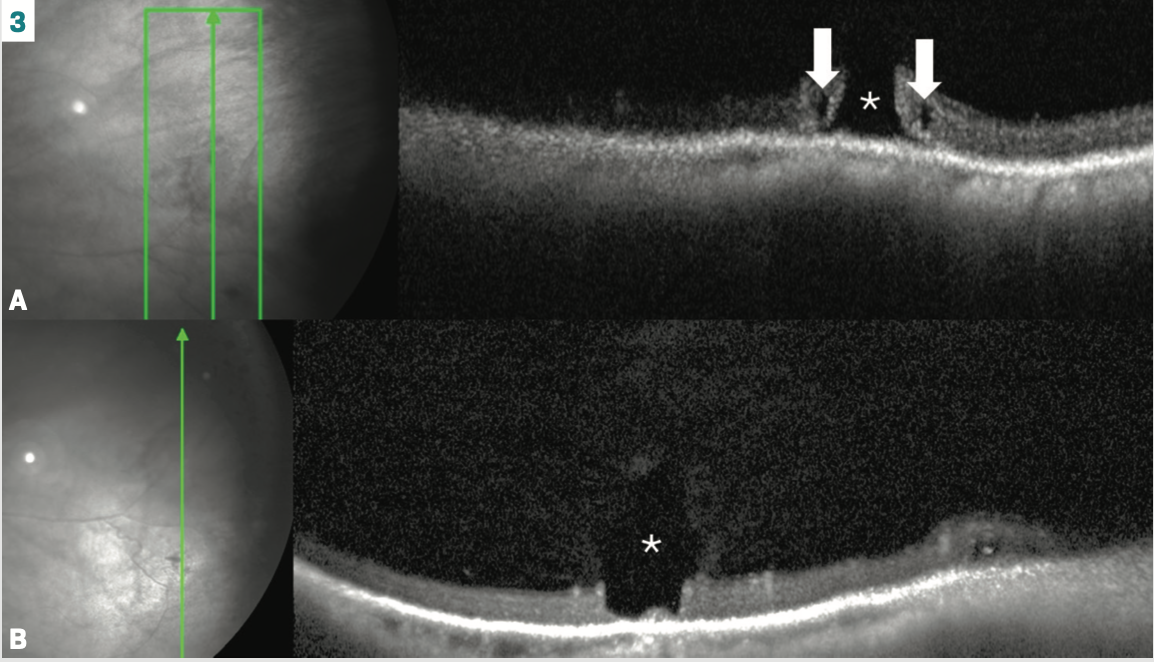

The significance here is illustrated in Figure 3A, which shows a full-thickness atrophic hole. The worry here is that vitreous fluid now has potential access to the subretinal space, which could result in a retinal detachment. Contrast this to the partial thickness atrophic hole or retinal erosion in Figure 3B, where a small amount of retinal tissue remains, which is a barrier to any overlying fluid reaching the subretinal space.

The P-OCT appearance of full-thickness retinal atrophic holes varies. Specifically, the hole’s edges may be flat or everted, and sometimes cystoid degeneration surrounds the area.5 When these are located with lattice, they rarely result in a progressive retinal detachment.6 In the American Academy of Ophthalmology’s Preferred Practice Patterns (PPP), asymptomatic atrophic holes fall into the “treatment is rarely recommended” category.7 However, the PPP does not address what the hole looks like on P-OCT. Are elevated edges more at-risk than flat ones? Do cystic spaces infer any risk? As OCT technology continues to evolve, so may its introduction into current PPP.

Seeing is believing: lattice and vitreoretinal interaction

Lattice degeneration presents in about 10% of patients, with a 50% chance of bilaterality.6,10 Retinal thinning is a common finding.10 Exaggerated vitreoretinal attachments and overlying vitreous liquefaction tend to occur (Figure 3B, asterisk). The vitreous traction can be striking with P-OCT (Figure 5A). It is no wonder, then, that lattice poses a risk, albeit small, for retinal detachment.